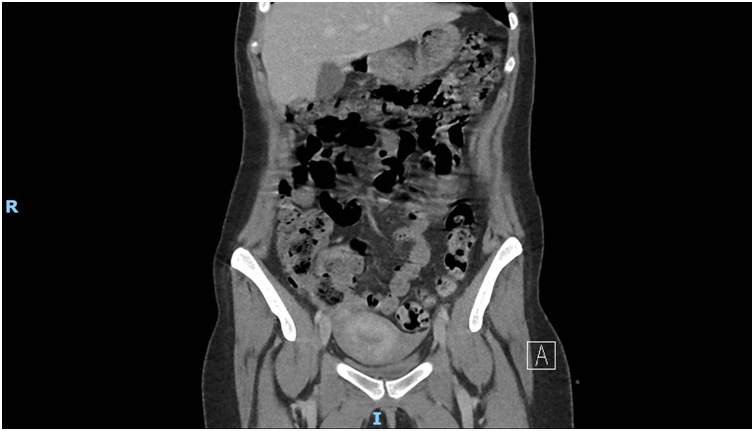

Imaging via MRI and CT demonstrated a complex, encapsulated lesion with peripheral enhancement and restricted diffusion. Multidisciplinary evaluation suggested a congenital epidermoid or duplication cyst. Given the absence of malignancy and surgical complexity, a conservative management strategy was adopted.

Figure 3: Figure 3 Duplication cyst 2020 Coronal plane